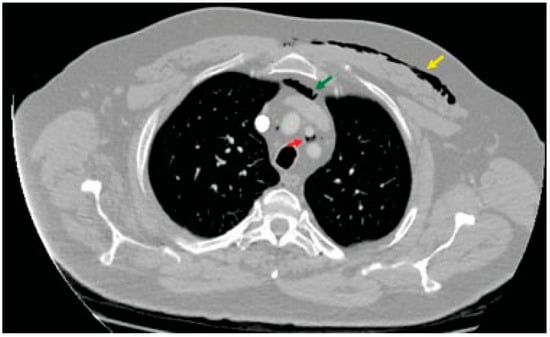

Acute Hyponasality (Closed Rhinolalia) and Craniomaxillofacial Fracture Suggest the Coexistence of Retropharyngeal Emphysema and Pneumomediastinum

Case Report